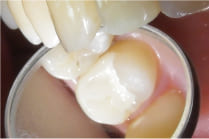

部分が小さければC2のインレーでも対応できる場合もありますが、歯が残せる状態ではあるも

のの、大きい場合はセラミッククラウン(銀歯のセラミック版です)をかぶせる処置を

行います。

セラミッククラウンだと、お口を開けた時でも銀歯のように目立ちにくいのがポイントです。

1回目の治療時に虫歯を取って、根の治療を行ったのち、仮歯をいれました。

このような状態でもすぐに見た目が気にならなくなりました。

その後根の治療をし、土台をいれてから口腔内スキャナーでスキャンしました。

スキャンデータを用いて、ジルコニアセラミックを作成し歯にかぶせて治療終了です。

治療回数は7回でした。

術後は見た目だけでなく、噛み合わせや口腔内の健康も大きく改善されました。

当院では1回目に仮歯を入れますので、変色や欠けた部分がすぐなくなります。